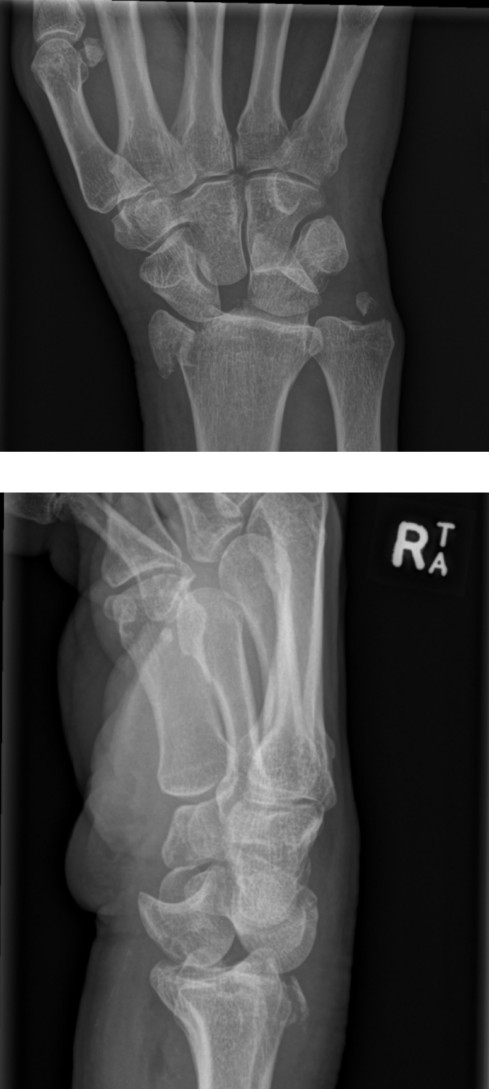

Wrist injury

A 55-year-old woman has fallen and presents with a deformed wrist. Her X-ray is shown below: